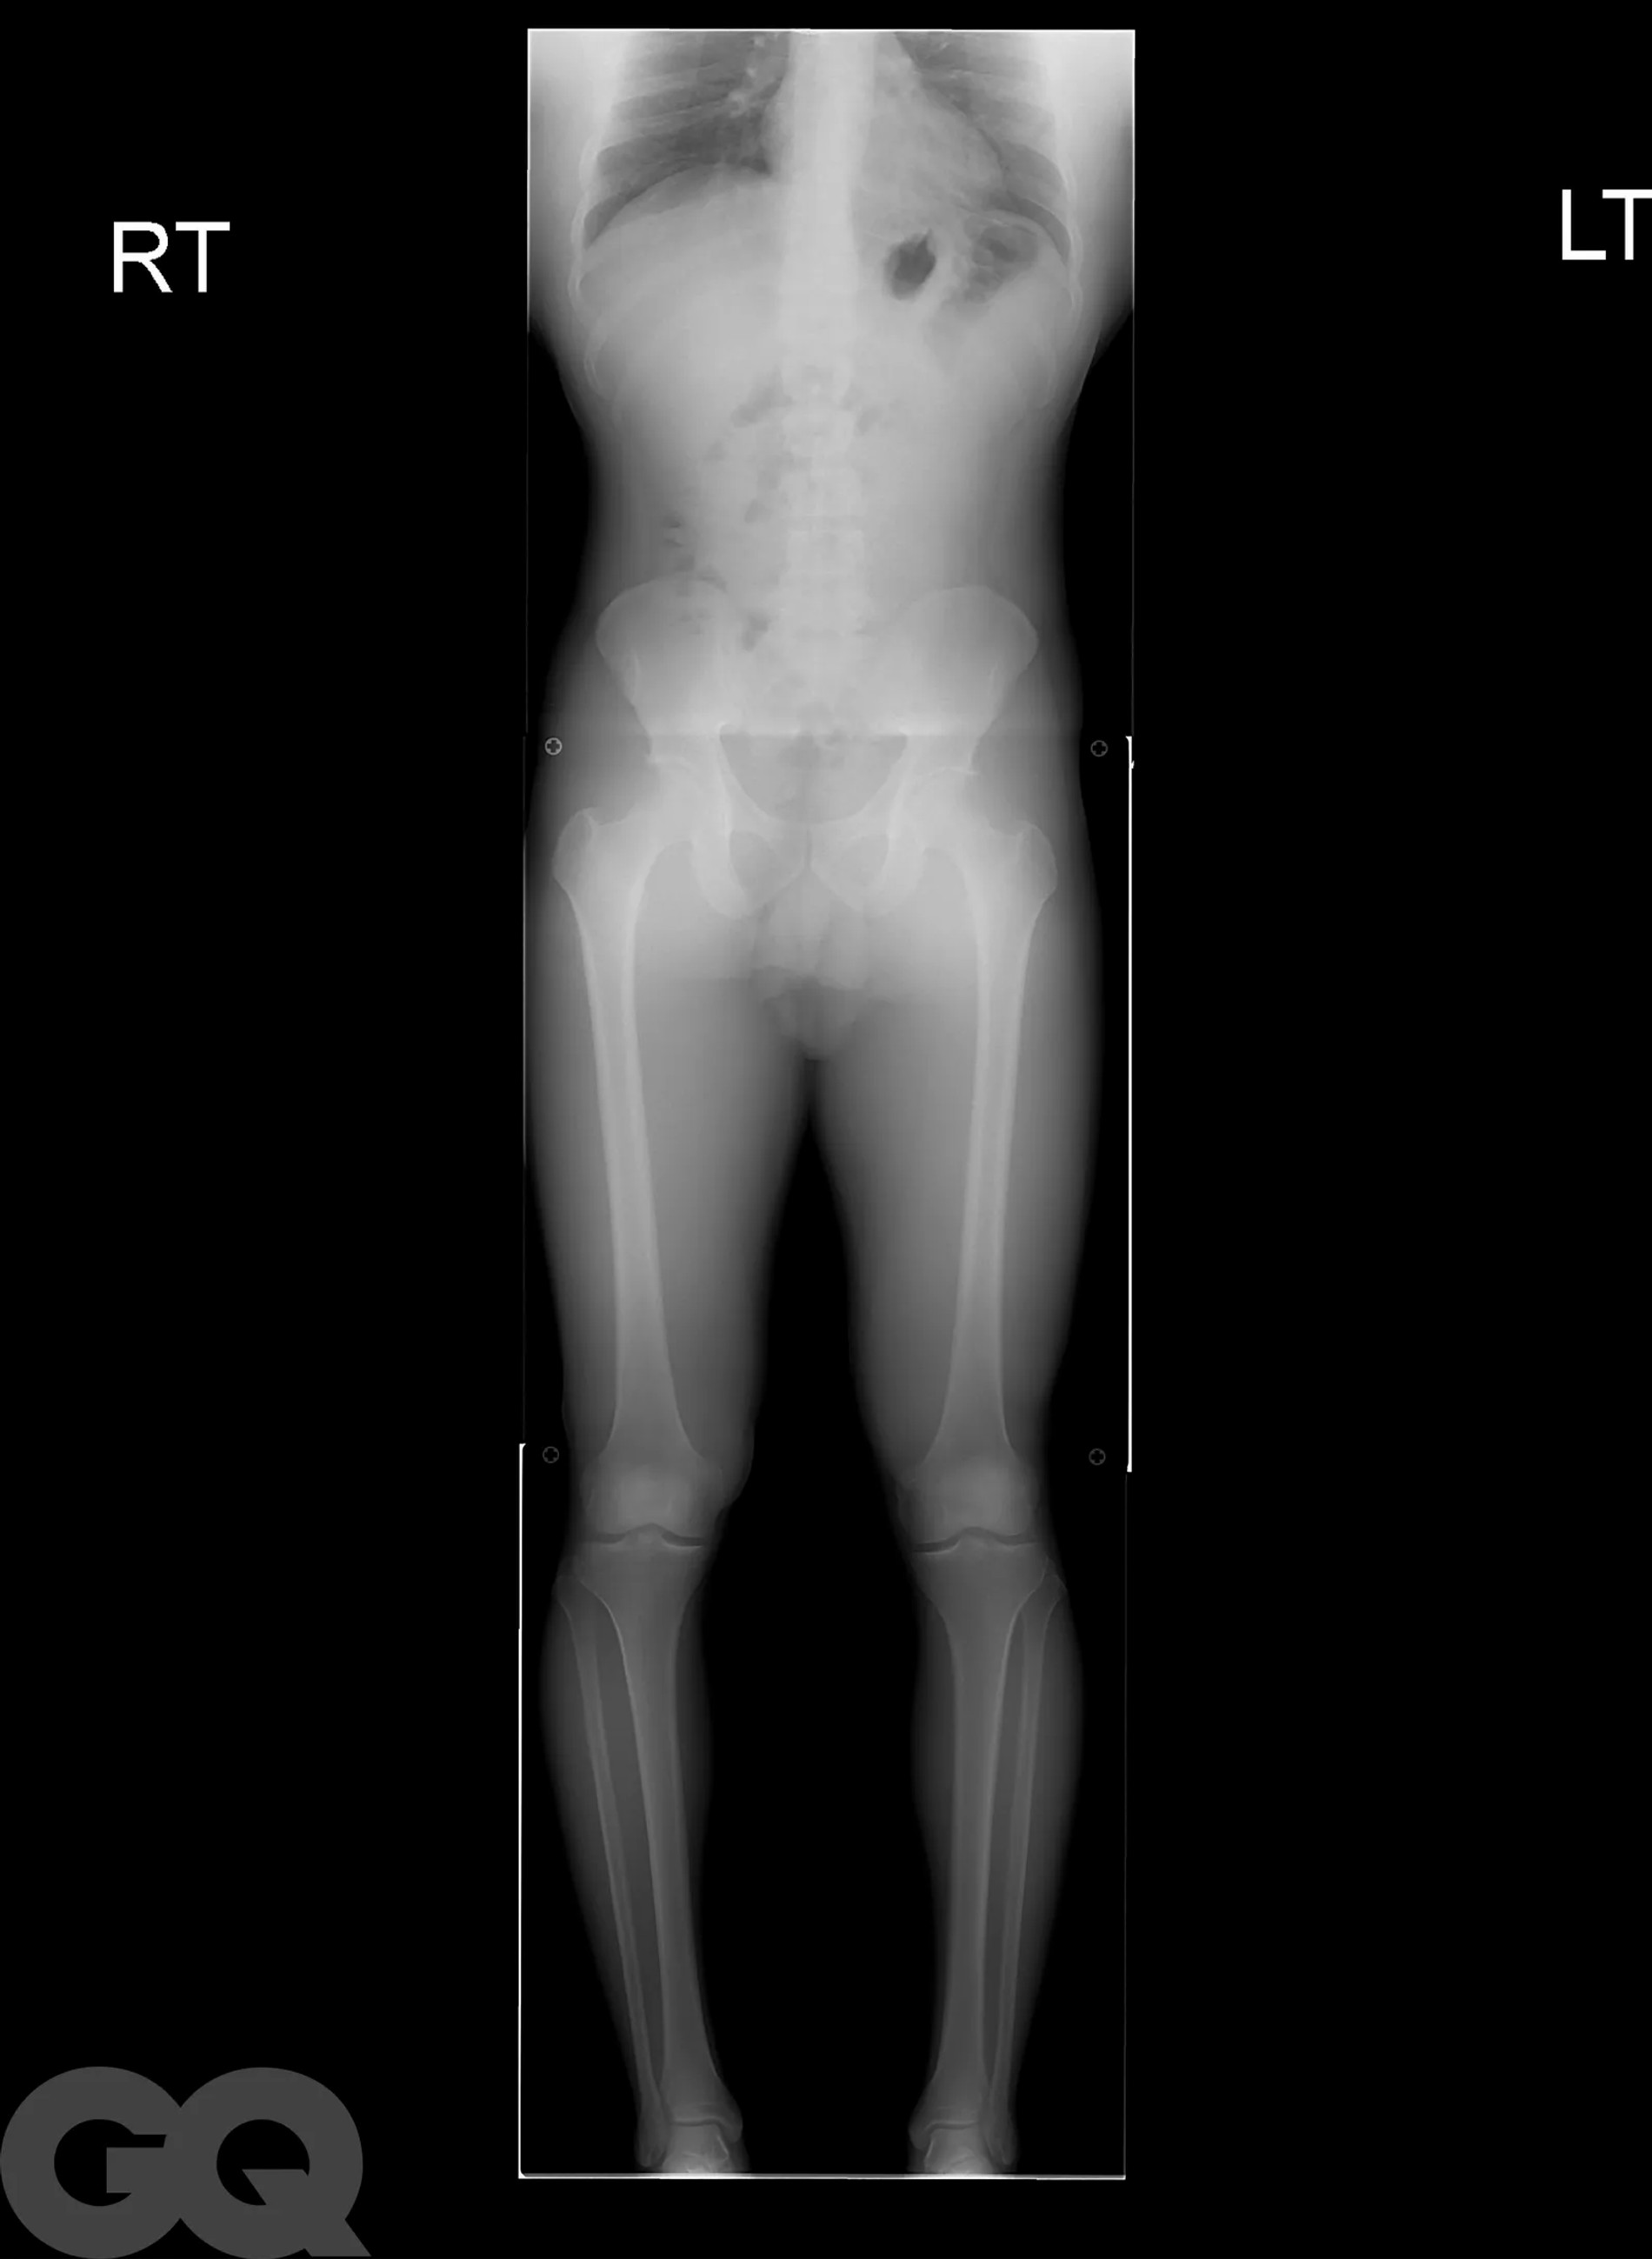

Надо сказать, что операция эта больше напоминает самую настоящую экзекуцию. Она основана на методике советского хирурга-ортопеда Гавриила Илизарова, которая изначально была разработана для пациентов со сложными переломами костей. Американские специалисты ее доработали и сделали более щадящей, но все же. В погоне за несколькими добавочными сантиметрами мужчины соглашаются на то, чтобы их собственные бедренные кости были сломаны. Да, без этого никак.

После перелома между костями вставляют регулируемые титановые стержни, которые наращивают на один миллиметр каждый день в течение примерно 90 суток с помощью магнитного пульта дистанционного управления. Как только сломанные кости срастутся, человек становится выше ростом и снова может ходить. Обычно весь процесс занимает 1 год, реабилитация сопровождается болью, что нисколько не смущает мужчин, решивших немного подрасти.

Не останавливает их и тот факт, что удовольствие это, прямо скажем, из дорогих: мужчины раскошеливаются на суммы от 70 до 150 тысяч долларов, в зависимости от того, сколько дюймов они хотят нарастить. И даже берут на подобные цели кредиты! Большинство выбирают стандартные три дюйма — это при условии, что экзекуции подвергнутся только бедра. Если и этого недостаточно и хочется еще немножко подрасти, спустя время врачи предлагают таким же образом переделать и голени.